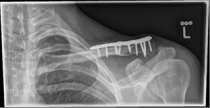

For severely displaced fractures, which do not allow for an independent coalescence of the fractured ends, or at risk of the surrounding soft-tissue mantle, an operative care should be performed. For fractures that lie in the shaft area of ​​the bone, this is done with a titanium plate, with additional lag screws, it should cause optimal compression of the fragments.

Picture 2: After the operation, the fracture is correctly repositioned and held in position with a titanium plate and two screws..